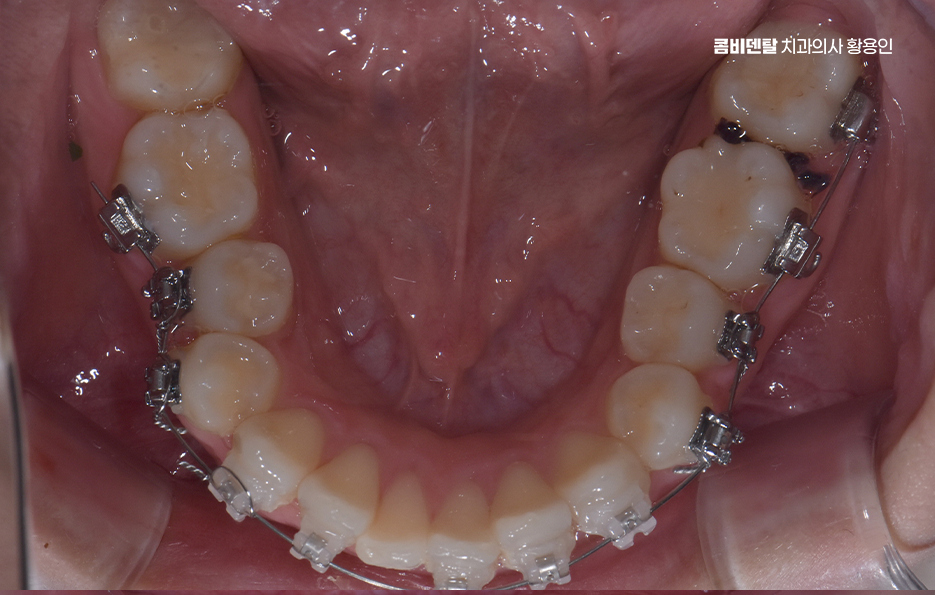

비발치 돌출입 교정 가능한 대표적인 케이스는 치아 배열의 공간이 비교적 충분한 경우로서 치아가 전체적으로 가지런하지는 않지만, 심하게 겹쳐 있지 않고 잇몸뼈 안에 어느 정도 여유 공간이 있는 경우에는 발치 없이도 치아를 뒤쪽으로 이동시키는 것이 가능한 경우가 있었어요.

비발치 돌출입 교정에서 주로 사용되는 방법 중 하나는 악궁 확장으로 치아가 나 있는 폭을 넓혀서 공간을 확보한 뒤, 치아를 재배열하는 방식인데 이 방법은 공간을 만들어 발치 없이 교정을 진행할 수 있다는 장점이 있지만, 무리한 확장은 잇몸이나 치아 뿌리에 부담을 줄 수 있기 때문에 한계 범위 안에서만 적용되고 있어요

또 다른 비발치 방법은 어금니를 뒤쪽으로 이동시키는 방식으로 어금니를 뒤로 보내서 앞니가 들어갈 공간을 만드는 개념이며 치간 삭제 라는 방법도 있는데 치아 사이의 공간을 미세하게 조절하여 치아의 건강은 해치지 않으면서 치아의 이동 공간을 확보하는 방식이라 할 수 있었어요

따라서 돌출입 비발치 교정을 고려할 때 중요한 것은 나에게 어떤 방식이 적합한지를 잘 따지는 것이며 기술적으로 비발치가 가능하다고 해서, 그 방법이 가장 좋은 선택이라는 의미는 아닐 수 있으며 현재 치아 상태, 얼굴 인상 변화에 대한 기대, 잇몸 건강, 장기적인 안정성까지 함께 고려해서 치료 계획을 세워야 하기 때문에 경험 많은 교정 전문의와 먼저 충분히 상의하고 판단하실 필요가 있었어요